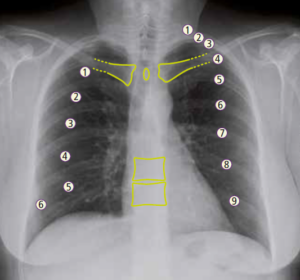

La DIAGNOSI si basa su:

- Rx faringo-esofageo con mezzo di contrasto baritato in proiezione antero-posteriore e laterale, valutando la sede, il volume e i rapporti del diverticolo: il mezzo di contrasto riempie il diverticolo mettendo in evidenza un livello idro-aereo in posizione di ortostasi, cioè il livello dove finisce la parte liquida, solida o semisolida e comincia la parte aerea.

- Esame endoscopico consente di evidenziare il colletto del diverticolo, lo stato della mucosa che può essere infiammata o ulcerata in seguito ad episodi di esofagite da reflusso.

L’endoscopia deve essere eseguita con molta cautela perché c’è il rischio di perforare la parete del diverticolo che è sottile e fragile.